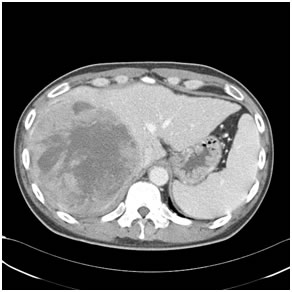

Large HCC in seg 2 & 3

Large HCC in seg 2&3